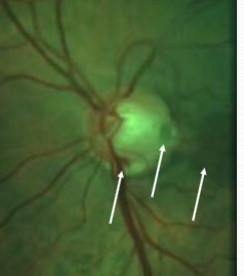

corkscrew prepapillary vascular loop

congenital

appearance:

aberrant development of retinal vasculature system (arterial usually but can be venous)

unilateral vessel loop arising from disc & returning to disc

extends up to 1/3 into vitreous cavity

may be partially enclosed w/ glial tissue

concurrent cilioretinal arteries in 75% of cases

complications:

must r/o acquired loops

rare BRAO/CRAO, TMB, recurrent vitreous hemorrhage, subretinal hemorrhage